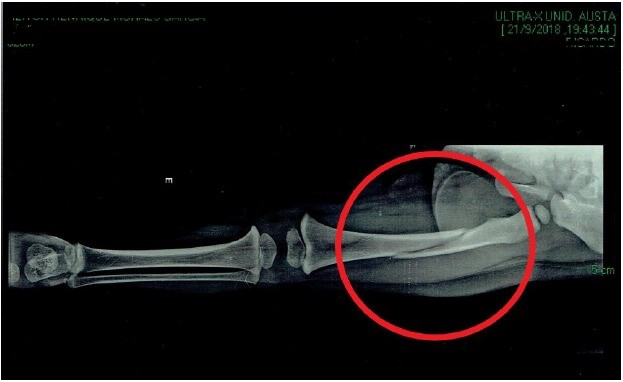

Ao chegar em casa, os pais notaram que o filho estava com a perna inchada e não conseguia ficar de pé, além de não parar de chorar. Eles levaram o menino ao hospital, local em que foi constatada fratura no fêmur da perna esquerda da criança.

De acordo com o pedido de indenização protocolado na Justiça, o menino teve de fazer uma operação chamada "redução incremento fratura fêmur” e ficar internado por quatro dias, além de ter tido duas pernas imobilizadas por 60 dias, dos quais ficou 40 dias com gesso. A criança andou mancando por quatro meses.

Raio-x comprovou a fratura no fêmur